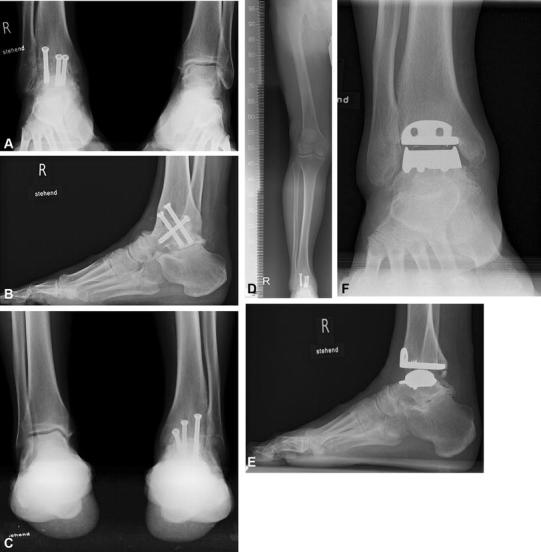

Высокоэффективным современным способом лечения данного заболевания является одномоментное артродезирование голеностопного и подтаранного суставов стержнем с блокированием. Операция артродезирования заключается в одновременном замыкании суставных поверхностей голеностопного и подтаранного суставов в правильном анатомическом положении, с внутренней фиксацией специальным стержнем.

Подобные вмешательства артродезирования голеностопного сустава уже более 25 лет широко выполняются в зарубежных клиниках и стали «золотым стандартом» для пациентов с выраженным артрозом голеностопного сустава, деформацией нижней трети голени и заднего отдела стопы. А также в случаях, когда эндопротезирование невозможно или неэффективно. В нашей стране данная высокотехнологическая операция выполняется только в единичных крупных федеральных клиниках, ожидание очереди на артродезирование голеностопного сустава может затянуться на многие месяцы, к сожалению эта операция недоступна большинству пациентов.

3. Эндопротезирование голеностопного сустава (эндопротез) — полная замена голеностопного сустава на искусственный.

Это сложная, высокотехнологичная операция, при успехе которой человек забывает о проблемах с голеностопным суставом на многие годы. В ходе операции хирург полностью удаляет суставные поверхности таранной и большеберцовой кости, и заменяет их металлическими имплантами, покрытыми полимерным материалом. Полимерный материал имеет низкий коэффициент трения и обеспечивает скольжение суставных поверхностей. Объём движений в суставе полный.

4. Создание артродеза — оперативное обездвиживание голеностопного сустава. В ходе операции происходит удаление суставных поверхностей голеностопного сустава, сопоставление обработанных поверхностей большеберцовой и таранной кости, и их фиксация. Через 4-6 месяцев наступает полное сращение этих костей. После проведения операции боли в голеностопном суставе прекращаются. Движения в суставе становятся невозможными. Однако, частично происходит компенсирование объёма движений за счёт других суставов стопы, что не приводит к значительному расстройству функции конечности в целом.

Операция по сращению голеностопного сустава: Эта операция, также называемая артродезом, используется при терминальной стадии артрита голеностопного сустава.Процедура уменьшает подвижность изношенной части сустава/хряща, что, в свою очередь, уменьшает боль. По словам доктора Арчера, сустав затем удерживается на месте с помощью стержня или пластин и винтов. Кости со временем срастаются.

Полная замена голеностопного сустава: В ходе этой процедуры поврежденные хрящи и кости удаляются и заменяются новыми металлическими или пластиковыми суставными поверхностями для восстановления функции сустава.

- Хирургия слияния : Этот вид хирургии, также называемый артродезом, включает сращивание костей с использованием стержней, штифтов, винтов или пластин. После заживления кости остаются сросшимися.

- Операция по замене сустава : Этот вид операции включает замену голеностопного сустава искусственными имплантатами и используется только в редких случаях.